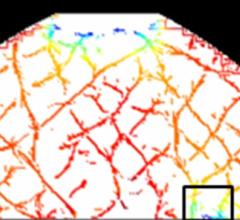

September 28, 2012 — New optical imaging technology developed at Tufts University School of Engineering could give doctors new ways to both identify breast cancer and monitor individual patients' response to initial treatment of the disease. A five-year clinical study of the procedure, funded by a $3.5 million grant from the National Institutes of Health, is now underway at Tufts Medical Center in Boston.